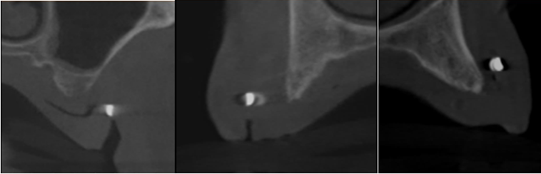

Insufficient bone height on 16 and 28, Insufficient bone width on 14 and 24.

Figure 9: Cross sectional cuts at location 16 -14 -11.

Figure 10: Paraaxial cuts of region 22-24-28.